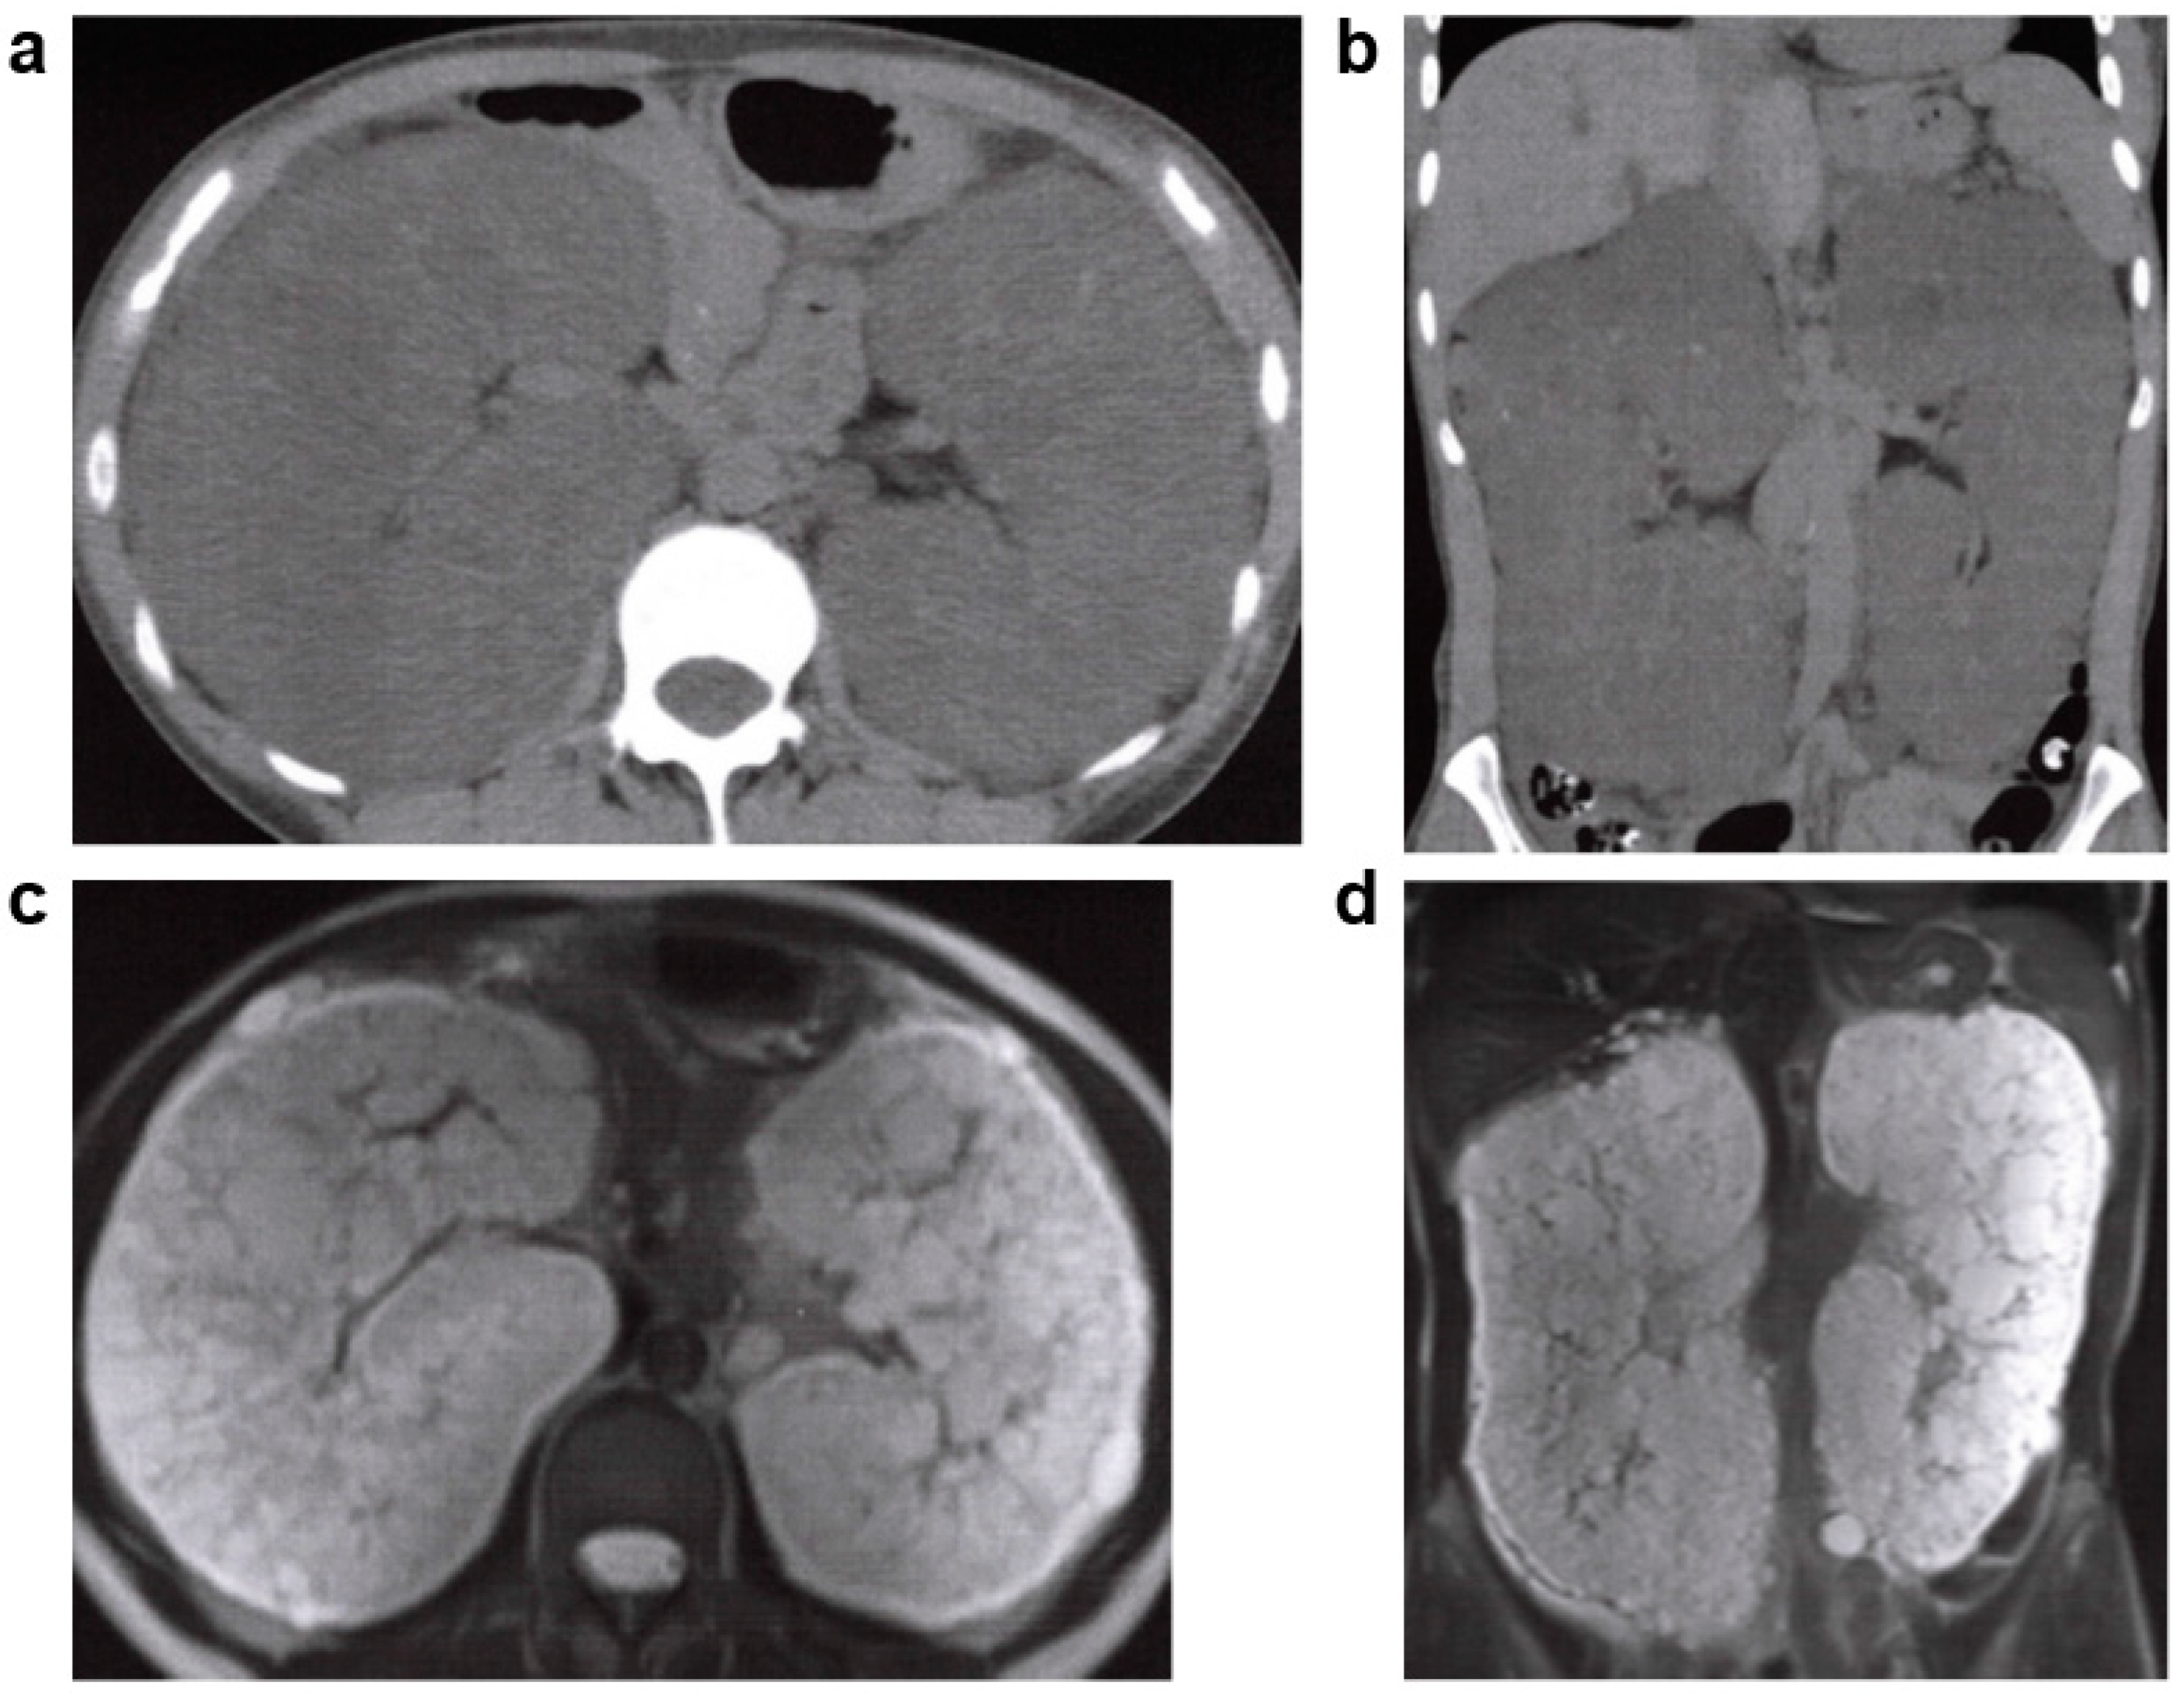

3.6.1. Tuberous Sclerosis (TSC)

- Curatolo, P.; Bombardieri, R.; Jozwiak, S. Tuberous sclerosis. Lancet 2008, 372, 657–668. [Google Scholar] [CrossRef]

- Dabora, S.L.; Jozwiak, S.; Franz, D.N.; Roberts, P.S.; Nieto, A.; Chung, J.; Choy, Y.S.; Reeve, M.P.; Thiele, E.; Egelhoff, J.C.; et al. Mutational analysis in a cohort of 224 tuberous sclerosis patients indicates increased severity of TSC2, compared with TSC1, disease in multiple organs. Am. J. Hum. Genet. 2001, 68, 64–80. [Google Scholar] [CrossRef] [PubMed]

- Rakowski, S.K.; Winterkorn, E.B.; Paul, E.; Steele, D.J.; Halpern, E.F.; Thiele, E.A. Renal manifestations of tuberous sclerosis complex: Incidence, prognosis, and predictive factors. Kidney Int. 2006, 70, 1777–1782. [Google Scholar] [CrossRef]

- Wataya-Kaneda, M.; Tanaka, M.; Hamasaki, T.; Katayama, I. Trends in the prevalence of tuberous sclerosis complex manifestations: An epidemiological study of 166 Japanese patients. PLoS ONE 2013, 8, e63910. [Google Scholar] [CrossRef]

- Umeoka, S.; Koyama, T.; Miki, Y.; Akai, M.; Tsutsui, K.; Togashi, K. Pictorial review of tuberous sclerosis in various organs. Radiographics 2008, 28, e32. [Google Scholar] [CrossRef]

- Schillinger, F.; Montagnac, R. Chronic renal failure and its treatment in tuberous sclerosis. Nephrol. Dial. Transpl. 1996, 11, 481–485. [Google Scholar] [CrossRef]

- Bissler, J.J.; Siroky, B.J.; Yin, H. Glomerulocystic kidney disease. Pediatr. Nephrol. 2010, 25, 2049–2056. [Google Scholar] [CrossRef]

- Siroky, B.J.; Towbin, A.J.; Trout, A.T.; Schäfer, H.; Thamann, A.R.; Agricola, K.D.; Tudor, C.; Capal, J.; Dixon, B.P.; Krueger, D.A.; et al. Improvement in Renal Cystic Disease of Tuberous Sclerosis Complex after Treatment with Mammalian Target of Rapamycin Inhibitor. J. Pediatr. 2017, 187, 318–322.e312. [Google Scholar] [CrossRef] [PubMed]

- Martignoni, G.; Bonetti, F.; Pea, M.; Tardanico, R.; Brunelli, M.; Eble, J.N. Renal disease in adults with TSC2/PKD1 contiguous gene syndrome. Am. J. Surg. Pathol. 2002, 26, 198–205. [Google Scholar] [CrossRef]

- Sampson, J.R.; Maheshwar, M.M.; Aspinwall, R.; Thompson, P.; Cheadle, J.P.; Ravine, D.; Roy, S.; Haan, E.; Bernstein, J.; Harris, P.C. Renal cystic disease in tuberous sclerosis: Role of the polycystic kidney disease 1 gene. Am. J. Hum. Genet. 1997, 61, 843–851. [Google Scholar] [CrossRef]

| TSC | TSC1, TSC2 | AD | 1/10,000 | Hamartoma in the skin, nervous system, kidney, lung, bone, and elsewhere. Renal lesions; angiomyolipoma (AML), renal cysts, renal cell carcinoma. |